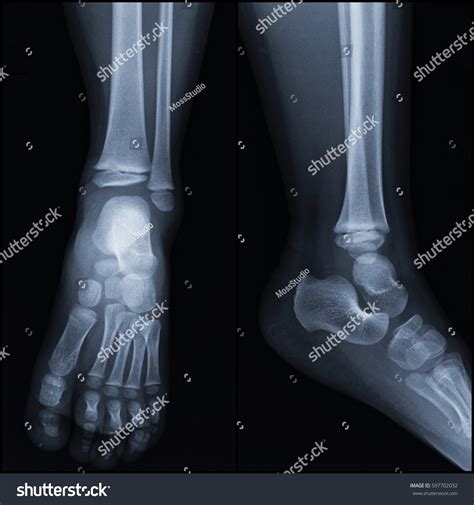

A Normal Ankle Xray is a radiographic image of the ankle joint that shows the bones, joints, and surrounding soft tissues. It is commonly used to diagnose fractures, dislocations, and other abnormalities in the ankle. The procedure is non-invasive and relatively quick, making it a preferred method for initial assessments.

3. Multiple images are taken from different angles to provide a comprehensive view of the ankle joint.

A Normal Ankle Xray typically shows the following structures clearly:

• Tibia and fibula (the two bones of the lower leg)

• Talus (the bone that forms the ankle joint)

• Calcaneus (the heel bone)

• Joint spaces and cartilage

In a normal X-ray, the bones should appear smooth and continuous, with no signs of fractures or dislocations. The joint spaces should be uniform, and there should be no evidence of bone spurs or other abnormalities.